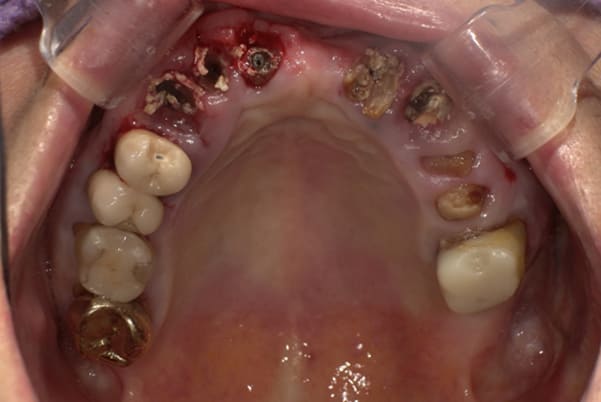

上顎治療前

-

上顎治療後

根のみの7本は虫歯にもなっており歯肉は腫れあがっています。

残りの歯もレントゲンで重度の歯周炎によりぐらぐらな状態でした。